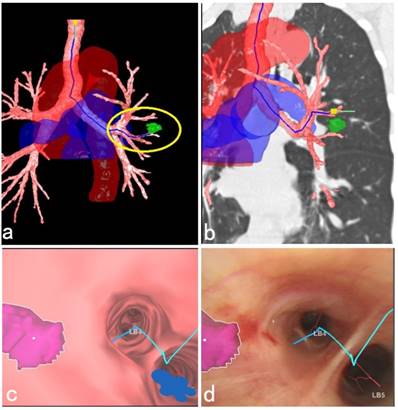

This study also suggested that the current R-EBUS needed to be improved in probing the depth of the peribronchial pulmonary lesions. Further, there was no doppler function equipped with the present ultrasonic radial probe, so it was not effective in distinguishing the peripheral blood vessels closed to the lesion, and this also caused bleeding complications during the needle puncture. In addition, for a peribronchial lesion located in the upper lobe, the C-TBNA procedure using 19G tissue needle combined with a therapeutic bronchoscope sometimes could not be implemented effectively due to limited bending angle of therapeutic bronchoscopic insertion part. Therefore, it is necessary to develop equipment for increasing the diagnostic yield in the future. Fortunately, updated C-TBNA techniques as well as new types of puncture needles for different puncture sites are now available, which have promoted renewal of C-TBNA [20, 21]. In addition, new advanced navigation systems, such as virtual bronchoscopic navigation (VBN) system could be used to evaluate the peribronchial lesions, guide the needle puncture site, angle and depth, as well as reconstruct the large blood vessels around bronchi, and the VBN system offers a more comprehensive and three-dimensional identification, especially in the adjacent relationship between peripheral blood vessels surrounding the lesion as well as the important organs. This helps the C-TBNA to be a safe and efficient method to further improve the diagnostic yield and reduce the complications of bleeding [22-24] (Figure 4).

Figure 4

3D anatomical schematic diagram of a peribronchial pulmonary lesion with surrounding structures reconstructed by the VBN system. (a) 3D anatomical schematic diagram reconstructed by the VBN system showed a peribronchial lesion located in the lingular lobe of left upper lobe, the tracheobronchial tree with surrounding large blood vessels. The green mark within the yellow circle showed the lesion (Lung Point® AR Bronchoscopic Navigation, Broncus Medical, Inc.). (b) The lesion could be easily recognized by the fluoroscopy with the help of combination imaging of 3D anatomical schematic diagram and coronary chest CT imaging. (c) The endobronchial location of the solitary peribronchial lesion was seen with the VBN bronchoscopy. (d) During bronchoscopic airway exam, the corresponding position of the peribronchial lesion was marked realtimely to assist the C-TBNA procedure to efficiently obtain the pathological tissue. The final cytological results showed no malignant findings. After 1 year follow-up, the lesion in the left upper lobe shrinked obviously.